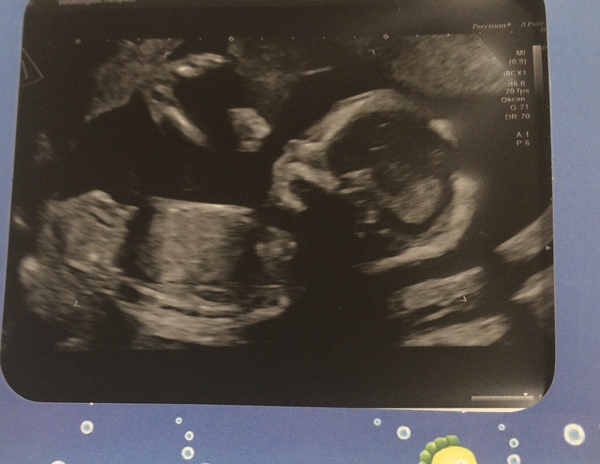

Hi all have been a bit quiet recently as I’ve been so worried about lack of movement. Scan today though and all is fine. And we’re having another girl! I’m over the moon. Placenta is at the front wall which is probably muffling some movement but otherwise fine and baby measuring comfortably on the 50th centile across the board.

Massive relief. And so much easier in terms of sorting clothes etc!

Lovely scan pic though very clear!